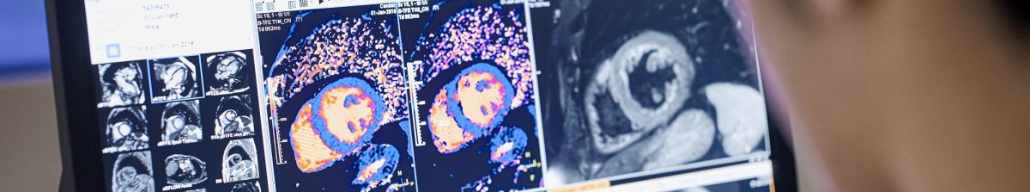

МРТ сердца vs ангиография у пациентов с подозрением на инфаркт

Фото из открытого источника (Яндекс-картинки)